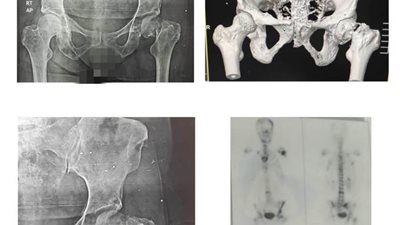

استبدال مفصل فخذ لمسنة بمستشفى ميت غمر المركزي

الخميس 25/فبراير/2021 - 02:43 م